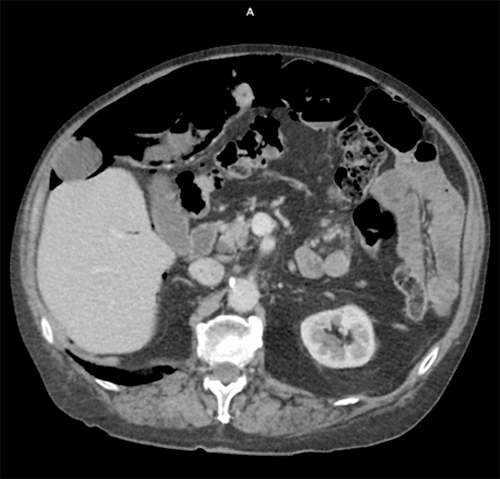

On arrival, he was afebrile and hemodynamically stable. Physical exam revealed mild epigastric tenderness but no rebound, guarding, distension, masses, or organomegaly. On rectal exam, he had dark stool that was guiac negative. His labs were significant for white blood cell count of 9,600/μL, creatinine of 1.3 mg/dL, and lactic acid of 1.47 mmol/L. A CT scan was obtained, which showed pneumatosis of the small bowel and extensive pneumoperitoneum, and he was urgently taken to the OR for concern of hollow viscous injury with possible bowel ischemia (Figure 1).

Figure 1. Small bowel pneumatosis with extensive pneumoperitoneum. No evidence of portal venous gas